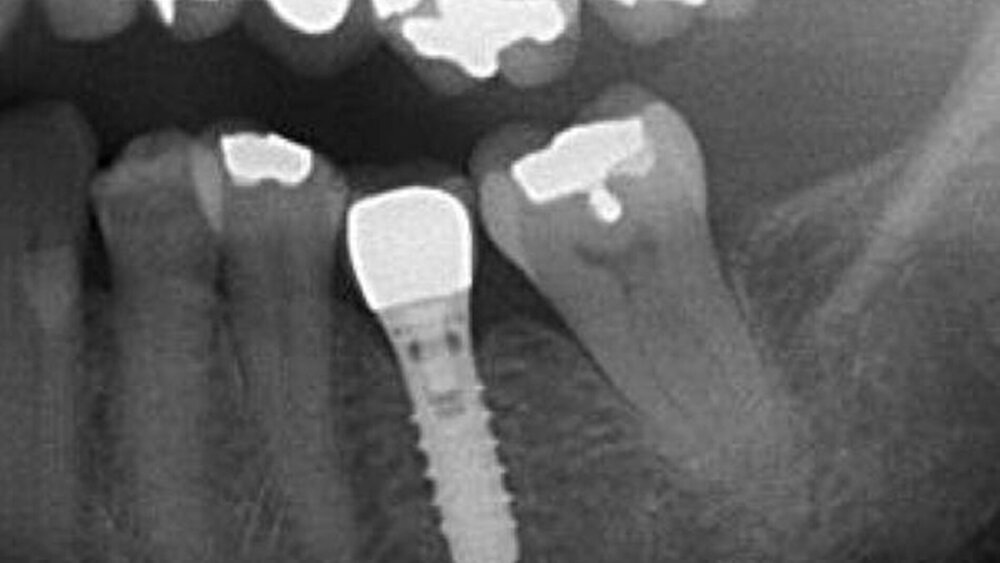

Bei 95 Patienten wurden 105 untere Molaren und Prämolaren nach Leitungsanästhesie des N. alveolaris inferior extrahiert (Abbildungen 1 und 2). In 53 Fällen wurde 2-prozentiges Articain (Gruppe I), in 52 Fällen 4-prozentiges Articain (Gruppe II) verabreicht.